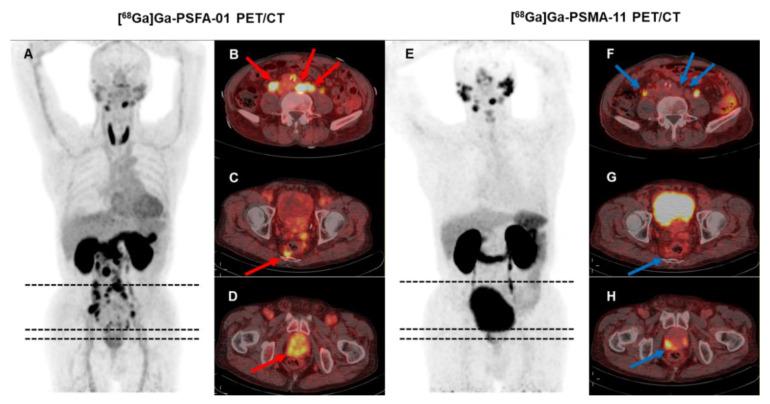

To assess the effectiveness of [Ga]Ga-PSFA-01 PET/CT in detecting primary tumors and metastatic lesions in patients with prostate cancer (PCa), and to compare the results with those from [Ga]Ga-PSMA-11 PET/CT and [Ga]Ga-FAPI-04 scans. Patients with histologically proven PCa were prospectively recruited and underwent [Ga]Ga-PSFA-01 PET/CT, of which: 25 participants also underwent [Ga]Ga-PSMA-11 PET/CT scan, 5 patients also underwent [Ga]Ga-FAPI-04 PET/CT scan, 3 patients underwent three modalities imaging. To assess the expression of PSMA and FAP, we obtained a pathological tissue section from a patient and performed immunohistochemical staining analysis. SUV, SUV, SUV and the number of detected lesions were compared by using the Wilcoxon signed-rank test, and the Mc-Nemar test was used to compare detectivity. Correlation between SUV and prostate cancer related clinical indicators was demonstrated with Spearman's ratio. A visual assessment was made to compare the detectability of primary tumors and metastases in different regions. A total of 33 patients with a median age of 70 years (range: 52-89 years) were enrolled. Including 13 patients for initial staging and 20 for recurrence detection. [Ga]Ga-PSFA-01 demonstrated superior performance in both patient-based and lesion-based analyses than [Ga]Ga-PSMA-11 PET/CT. However, [Ga]Ga-PSFA-01 depicted lower uptake in primary tumors (11.13 ± 7.04 vs. 15.44 ± 9.25, p = 0.009), bone metastases (8.50 ± 5.0 vs. 12.43 ± 9.55, p < 0.001) and metastases in other sites (6.05 ± 3.29 vs. 10.73 ± 8.74, p = 0.028) , lower tumor to background ratio (TBR) than [Ga]Ga-PSMA-11 PET/CT (2.86 ± 1.50 vs. 9.50 ± 5.62, p < 0.001). [Ga]Ga-PSFA-01 PET/CT showed more lesions (24 vs. 13, p = 0.18), higher uptake (primary tumors, 10.27 ± 2.42 vs. 7.32 ± 0.17, p = 0.109; bone metastases, 8.14 ± 5.98 vs.4.52 ± 1.22, p = 0.128; pelvic lymph nodes, 5.4 ± 2.83 vs.4.19 ± 1.39, p = 0.655) than [Ga]Ga-FAPI-04 PET/CT. There was also a significantly positive correlation between SUV of prostate lesions with the tPSA levels (r = 0.468, p = 0.016) and fPSA levels (r = 0.518, p = 0.04), a significantly negative correlation with the free-to-total prostate-specific antigen ratio (FPSAR) (r = -0.608, p = 0.012). [Ga]Ga-PSFA-01 PET/CT demonstrated higher detection rates and visual assessment efficacy compared to [Ga]Ga-PSMA-11 PET/CT in PCa patients. While preliminary data suggest that [Ga]Ga-PSFA-01 may also outperform [Ga]Ga-FAPI-04 PET/CT, the sample size for [Ga]Ga-FAPI-04 (n = 5) is limited, and further studies are needed to confirm these findings.

评估[镓]Ga-PSFA-01 PET/CT在检测前列腺癌(PCa)患者原发性肿瘤和转移病灶方面的有效性,并将结果与​​[镓]Ga-PSMA-11 PET/CT和[镓]Ga-FAPI-04扫描的结果进行比较。前瞻性招募经组织学证实为PCa的患者,并对其进行[镓]Ga-PSFA-01 PET/CT检查,其中:25名参与者还接受了[镓]Ga-PSMA-11 PET/CT扫描,5名患者还接受了[镓]Ga-FAPI-04 PET/CT扫描,3名患者接受了三种模式成像。为了评估PSMA和FAP的表达,我们从一名患者身上获取了病理组织切片并进行了免疫组织化学染色分析。使用Wilcoxon符号秩检验比较SUV、SUV、SUV和检测到的病灶数量,并使用Mc-Nemar检验比较检测率。用Spearman比率证明SUV与前列腺癌相关临床指标之间的相关性。进行视觉评估以比较不同区域原发性肿瘤和转移灶的可检测性。共纳入33例患者,中位年龄70岁(范围:52-89岁)。包括13例初始分期患者和20例复发检测患者。在基于患者和基于病灶的分析中,[镓]Ga-PSFA-01均表现出优于[镓]Ga-PSMA-11 PET/CT的性能。然而,[镓]Ga-PSFA-01在原发性肿瘤(11.13±7.04对15.44±9.25,p = 0.009)、骨转移(8.50±5.0对12.43±9.55,p <0.001)和其他部位转移(6.05±3.29对10.73±8.74,p = 0.028)中的摄取较低,肿瘤与背景比值(TBR)低于[镓]Ga-PSMA-11 PET/CT(2.86±1.50对9.50±5.62,p <0.001)。[镓]Ga-PSFA-01 PET/CT显示出比[镓]Ga-FAPI-04 PET/CT更多的病灶(24对13,p = 0.18)、更高的摄取(原发性肿瘤,10.27±2.42对7.32±0.17,p = 0.109;骨转移,8.14±5.98对4.52±1.22,p = 0.128;盆腔淋巴结,5.4±2.83对4.19±1.39,p = 0.655)。前列腺病灶的SUV与总前列腺特异性抗原(tPSA)水平(r = 0.468,p = 0.016)和游离前列腺特异性抗原(fPSA)水平(r = 0.518,p = 0.04)之间也存在显著正相关,与游离与总前列腺特异性抗原比值(FPSAR)存在显著负相关(r = -0.608,p = 0.012)。与[镓]Ga-PSMA-11 PET/CT相比,[镓]Ga-PSFA-01 PET/CT在PCa患者中显示出更高的检测率和视觉评估效能。虽然初步数据表明[镓]Ga-PSFA-01也可能优于[镓]Ga-FAPI-04 PET/CT,但[镓]Ga-FAPI-04的样本量(n = 5)有限,需要进一步研究来证实这些发现。